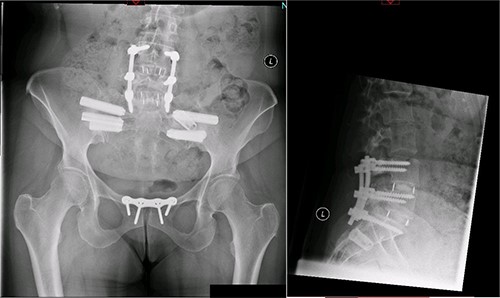

A magnetic resonance imaging (MRI) scan performed in October 2013 (Fig. 1) identified non-compressive, degenerated discs at L4/5 and L5/S1 vertebral levels. However, clinically as the patient was more tender over the left SI joint and the pubic symphysis (Fig. 2), a left sacroiliac joint fusion and symphysis pubis plating procedure was performed in August 2014 (Fig. 3). Following a short period of relief, the pain returned. Subsequently, the patient underwent a 360° fusion (front and back) of the L4/L5 and L5/S1 discs in August 2015 (Fig. 4), a year following the previous surgery. Once again, following a brief period of relief, the symptoms returned. The assumption then was that the initial fusion of the left sacroiliac joint had failed. Therefore, a revision fusion of the left sacroiliac joint and a primary fusion of the right sacroiliac joint was undertaken in August 2017 (Fig. 5).

Postoperative X-ray of the pelvis following the second fusion surgery: postoperative X-ray of the pelvis, performed in January 2016 following the second fusion surgery, showing 360° (front and back) fusion of the L4/5 and L5/S1 disc space.

Postoperative X-ray of the pelvis following the third fusion surgery: postoperative X-ray of the pelvis, performed in March 2021 following the third fusion surgery, showing refusion of the left sacroiliac joint and primary fusion of the right sacroiliac joint with the SI-bone implant.